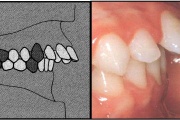

prognaatne hambumus, ülemised eeshambad on ettepoole alumiste suhtes ja eest

progeenne hambumus; alumised eeshambad on ettepoole ülemiste suhtes;